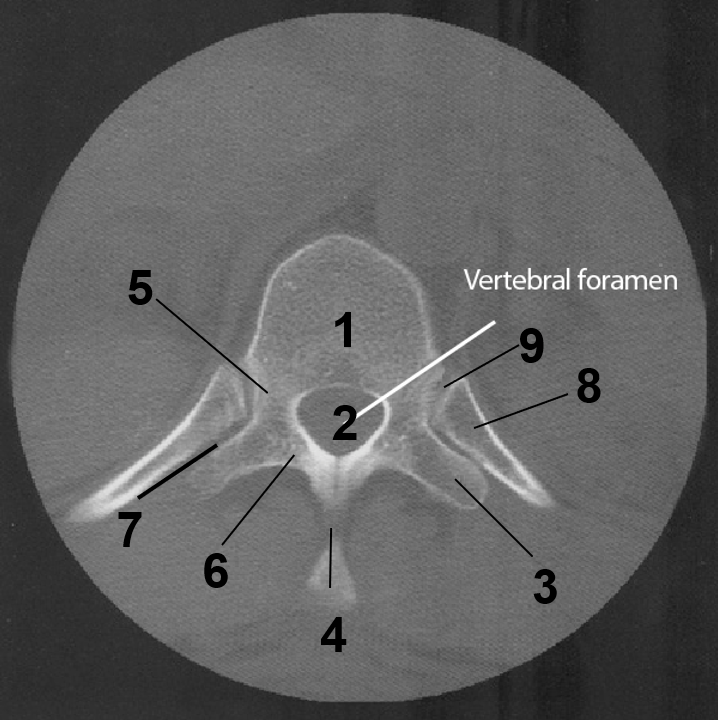

1

Body of of C7

2

Transverse foramen

3

Transverse process

4

Spinous Process

5

Vertebral Foramen

6

Lamina

7

Pedicle